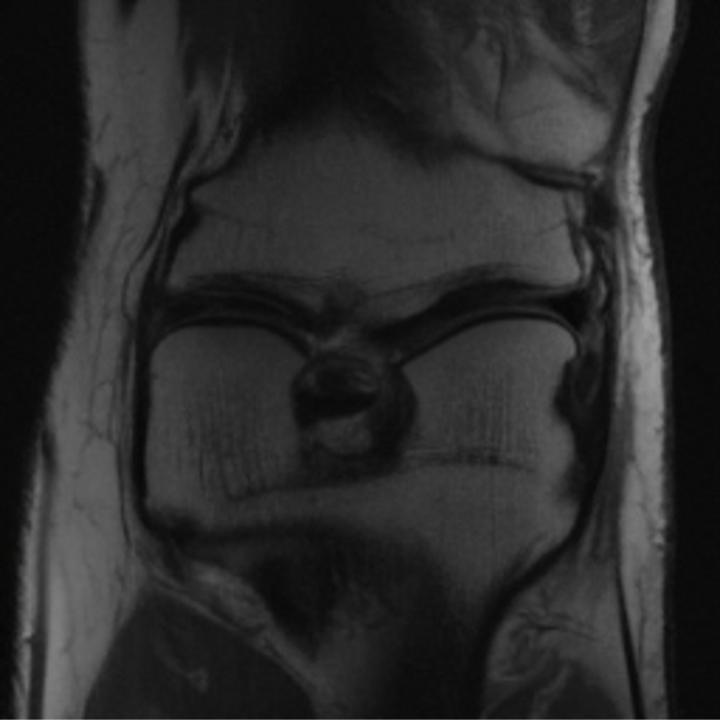

Notably, X-Diffusion achieves sota dB for a few input slices while baselines require more than 60 input slices to achieve similar performance (Figure 7). The margin is more than 12 dB PSNR for the 1-slice input in both the BRATS and the UK Biobank benchmarks (see Table 1 and Figure 6). For reference, two randomly sampled MRIs from the UK Biobank would have a PSNR of 15.95 dB 0.36 (on 4800 randomly sampled examples). The slices from 3D reconstructed volumes at varying depths and axis of rotation visually match the ground truths (see Figures 5 and Figure 4). We also plot the error map (Figure 4) of such X-Diffusion generations to highlight the differences with the ground truth MRIs.

One way to test the generalization capability of the trained X-Diffusion is to test it on a completely different domain from an MRI dataset not seen during training. We report the single-slice results on the test set of knees from NYU fastMRI [33, 80], using the X-Diffusion trained on the BRATS brain MRIs. The test PSNR result is 34.17 and an example is shown in Figure 8. It shows how successfully X-Diffusion can generate knee MRIs (out-of-domain) despite being trained on brains.